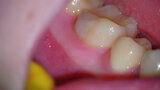

Fig. 4: Clinical image of tooth #46 showing swelling of the buccal mucosa and the presence of a sinus tract, as well as bleeding and pus after probing.